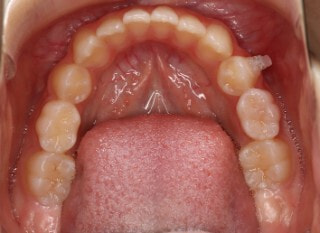

治療前